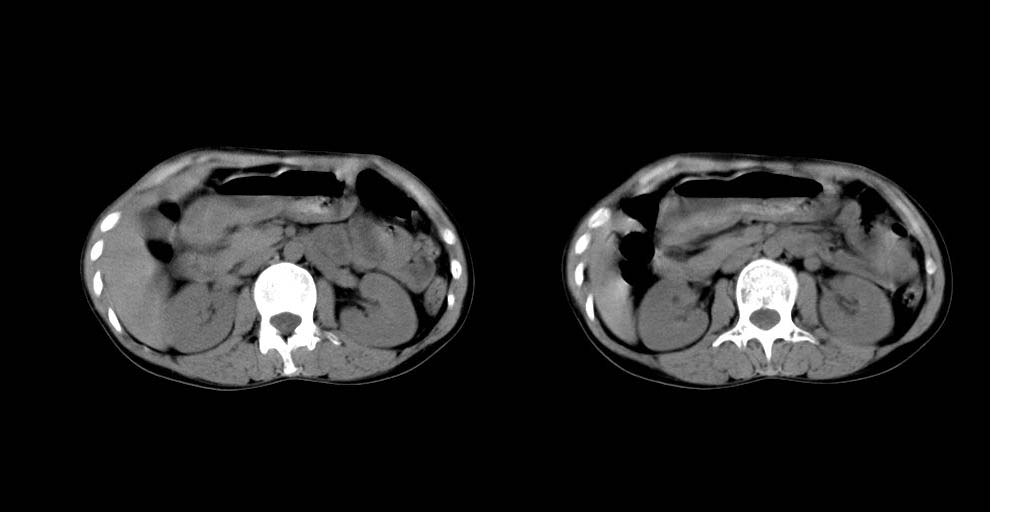

病人资料:女 30岁 右上腹部疼6天余.无其他不适,我院血常规正常,胸片正常,b超示1,肝内多发性结石.2,肝实质内似见结节影,占位病变待定.

考虑:1、肝右叶前段包膜下钙化灶;

2、肝胆胰脾ct平扫未见明显异常肿块影。

肝右叶小圆形低密度影,建议增强扫描

建议增强检查,平扫也显示脾肿大。

肝右叶前段包膜下钙化灶;做ct增强或mri。